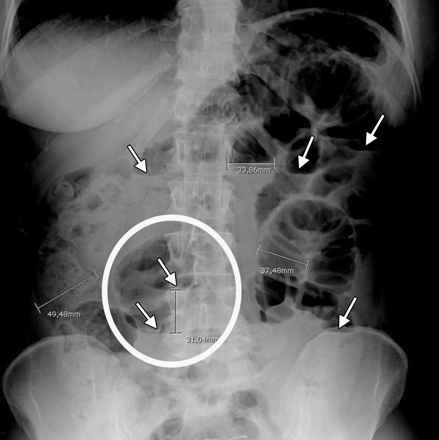

Chụp X-quang là một xét nghiệm ban đầu được thực hiện để chẩn đoán tắc ruột. Các phát hiện trên phim chụp X-quang gợi ý tắc ruột bao gồm các quai ruột giãn với mức khí – dịch, ruột xẹp ở đoạn xa, không có khí trong bụng hoặc có cách khác là dấu hiệu "chuỗi ngọc" cho thấy đầy hơi bị kẹt trong thành ruột.

Phương tiện hình ảnh học với x quang bụng chỉ có độ nhạy 50-60% đối với tắc ruột non. Trong hầu hết các trường hợp, X quang bụng sẽ có các đặc điểm gợi ý khả năng tắc ruột non như sau:

- Các quai ruột non giãn ra gần đến chỗ tắc nghẽn

- Các vòng quai ruột giãn nở tập trung ở vùng trung tâm

- Đường kính của quai ruột giãn từ trên 2,5 - 3 cm là đạt yếu tố cần thiết hướng tới chẩn đoán tắc ruột

- Quan sát thấy các nếp vòng ở ruột non, chạy vòng quanh chu vi ruột

- Có mực nước hơi nằm ở vùng trung tâm

- Trong cùng một vòng ruột nhưng mực nước hơi ở các độ cao khác nhau (chiều cao chênh lệch từ trên 2 cm).

Bụng chướng đầy hơi. Tuy nhiên, nếu phim chụp x quang tắc ruột non không thấy dấu hiệu này thì cũng không thể loại trừ được chẩn đoán. Nguyên nhân là vì trong tắc ruột non là tắc ruột cao, bụng có thể ít khả năng bị chướng khí hơn so với tắc ruột thấp như tắc đại tràng, do khí thoát ra ngoài qua phản xạ nôn ói của người bệnh hay đã được giải áp khi đặt ống thông dạ dày.

Dấu hiệu “chuỗi ngọc”: các túi khí nhỏ trong thành ruột khi trong lòng ruột non chứa đầy chất dịch